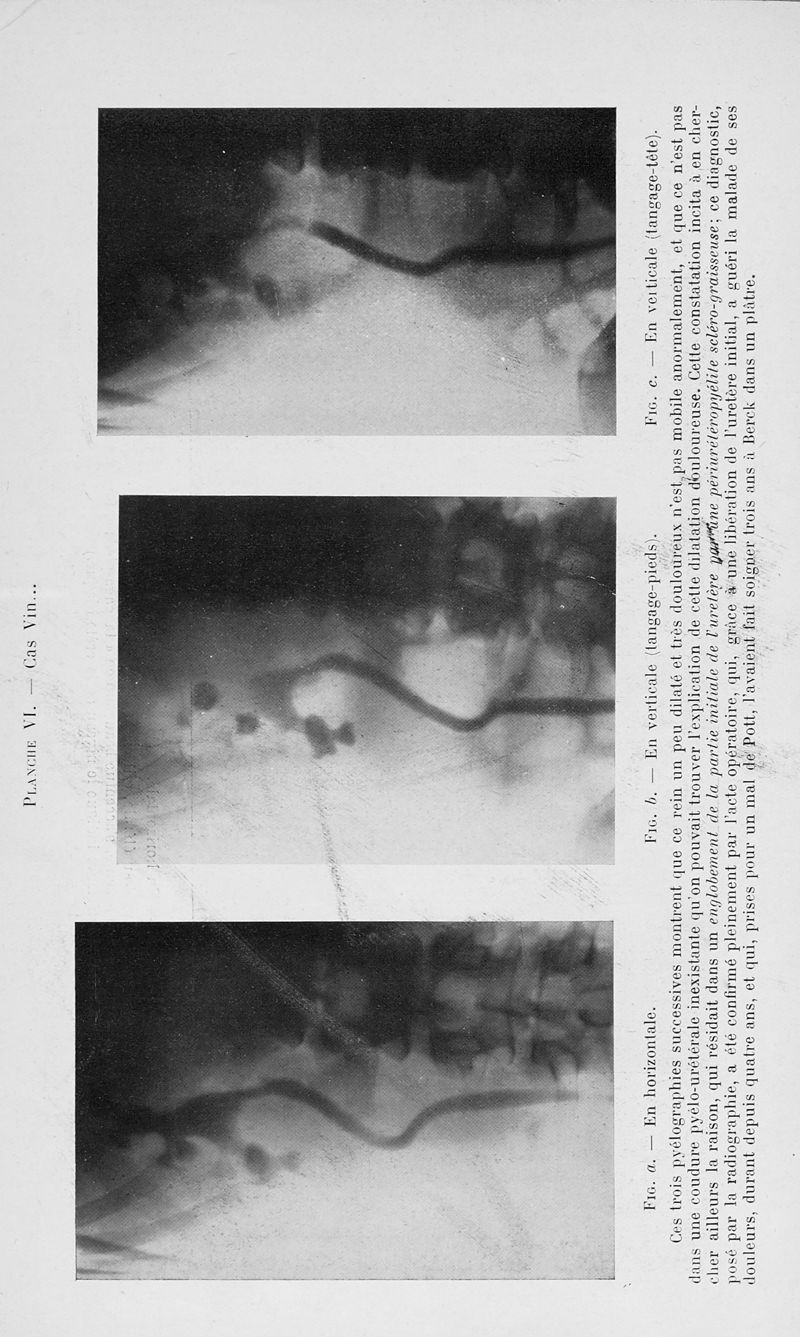

Bulletins et mémoires de la société nationale de chirurgie

Tome LXI, 1935. - Paris : Masson, 1935.